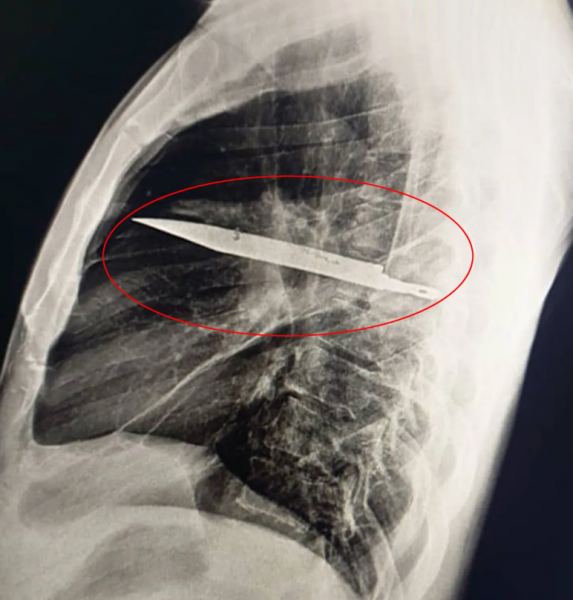

A chest X-ray eventually solved the mystery.

The results showed a blade inside the man’s chest cavity. Incredibly, the knife entered through the man’s right shoulder blade and somehow missed all his major organs.

Surgeons immediately performed an operation to carefully remove the blade and drain the pus caused by dead tissue.